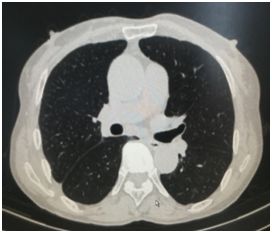

患者某老年男性,因胸闷喘憋入院,胸部CT提示右侧大量液胸(图1),在外院抽液后胸腔积液反复出现,长期诊断不清,家属非常着急,入科后与患者及家属沟通后果断选择了局麻胸腔镜检查,发现肺表面散在粟粒样结节,遂行脏层胸膜结节活检,术后3天病理即提示腺癌,在我院应用肺癌靶向药物克唑替尼治疗。目前健康生活已两年余,近日复查胸部CT肺部肿瘤消失,未见胸腔积液(图2)

图2